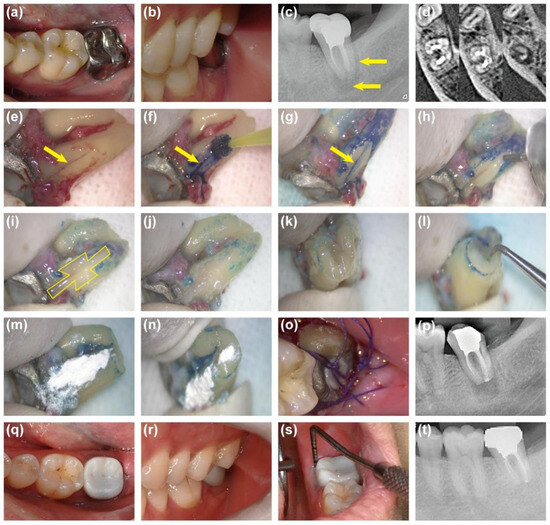

Case Report

A Novel Surgical Treatment Approach for Vertical Root Fractures of Endodontically Treated Molars: A Report of 3 Cases

by Nuo Chen, Chang Lu, Xinling He, Yuexing Zheng, Ying Yang and Wei Fan

J. Clin. Med. 2025, 14(24), 8966; https://doi.org/10.3390/jcm14248966 (registering DOI) - 18 Dec 2025

Viewed by 150

Abstract

Background: Vertical root fracture (VRF) is a severe complication of endodontically treated teeth with a poor prognosis. Despite many tentative tooth-preserving approaches, the current main treatment remains tooth extraction or root resection, which is largely due to the difficulty in balancing the mechanical [...] Read more.

Background: Vertical root fracture (VRF) is a severe complication of endodontically treated teeth with a poor prognosis. Despite many tentative tooth-preserving approaches, the current main treatment remains tooth extraction or root resection, which is largely due to the difficulty in balancing the mechanical strength for fracture fixation and biological properties for periodontal healing. Moreover, all documented reports regarding VRF repairing so far were limited to anterior teeth and premolars. Thus, the objective of this case report was to present a novel surgical treatment approach for repairing VRF of molars. Methods: Three patients (2 females, 1 male; aged 30–33 years) with endodontically treated molars (Tooth #46, #16, #37) diagnosed with VRF were treated with a dual-layered repair approach with modified fracture lines and retention forms through intentional replantation. Results: After 18, 21, and 36 months of follow-up, respectively, all three cases showed no clinical symptoms, normal tooth mobility and periodontal probing, as well as reduced periradicular radiolucency on radiographs. Root resorption or ankylosis was not observed. Conclusions: The novel surgical treatment approach demonstrates effectiveness in preserving endodontically treated molars with VRF, but its long-term treatment results for various VRF of molars need further randomized and controlled clinical investigations. Full article

(This article belongs to the Section Dentistry, Oral Surgery and Oral Medicine)

Show Figures

Figure 1